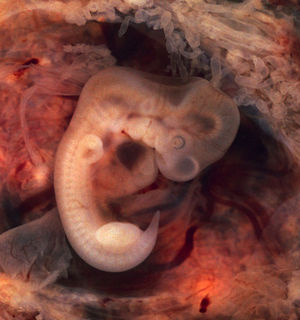

7、尾椎骨

尾椎骨,也成为尾骨,是人类椎骨的最后一个部分,也可以说是人类失去的尾巴的残余。实际上,地球上几乎所有的哺乳动物都或多或少有带着尾巴的影子,即使是在子宫发育的时候。对于人类来说就是如此。人类胚胎发育的某些阶段,可以很清楚的看出有尾巴形状的组织。